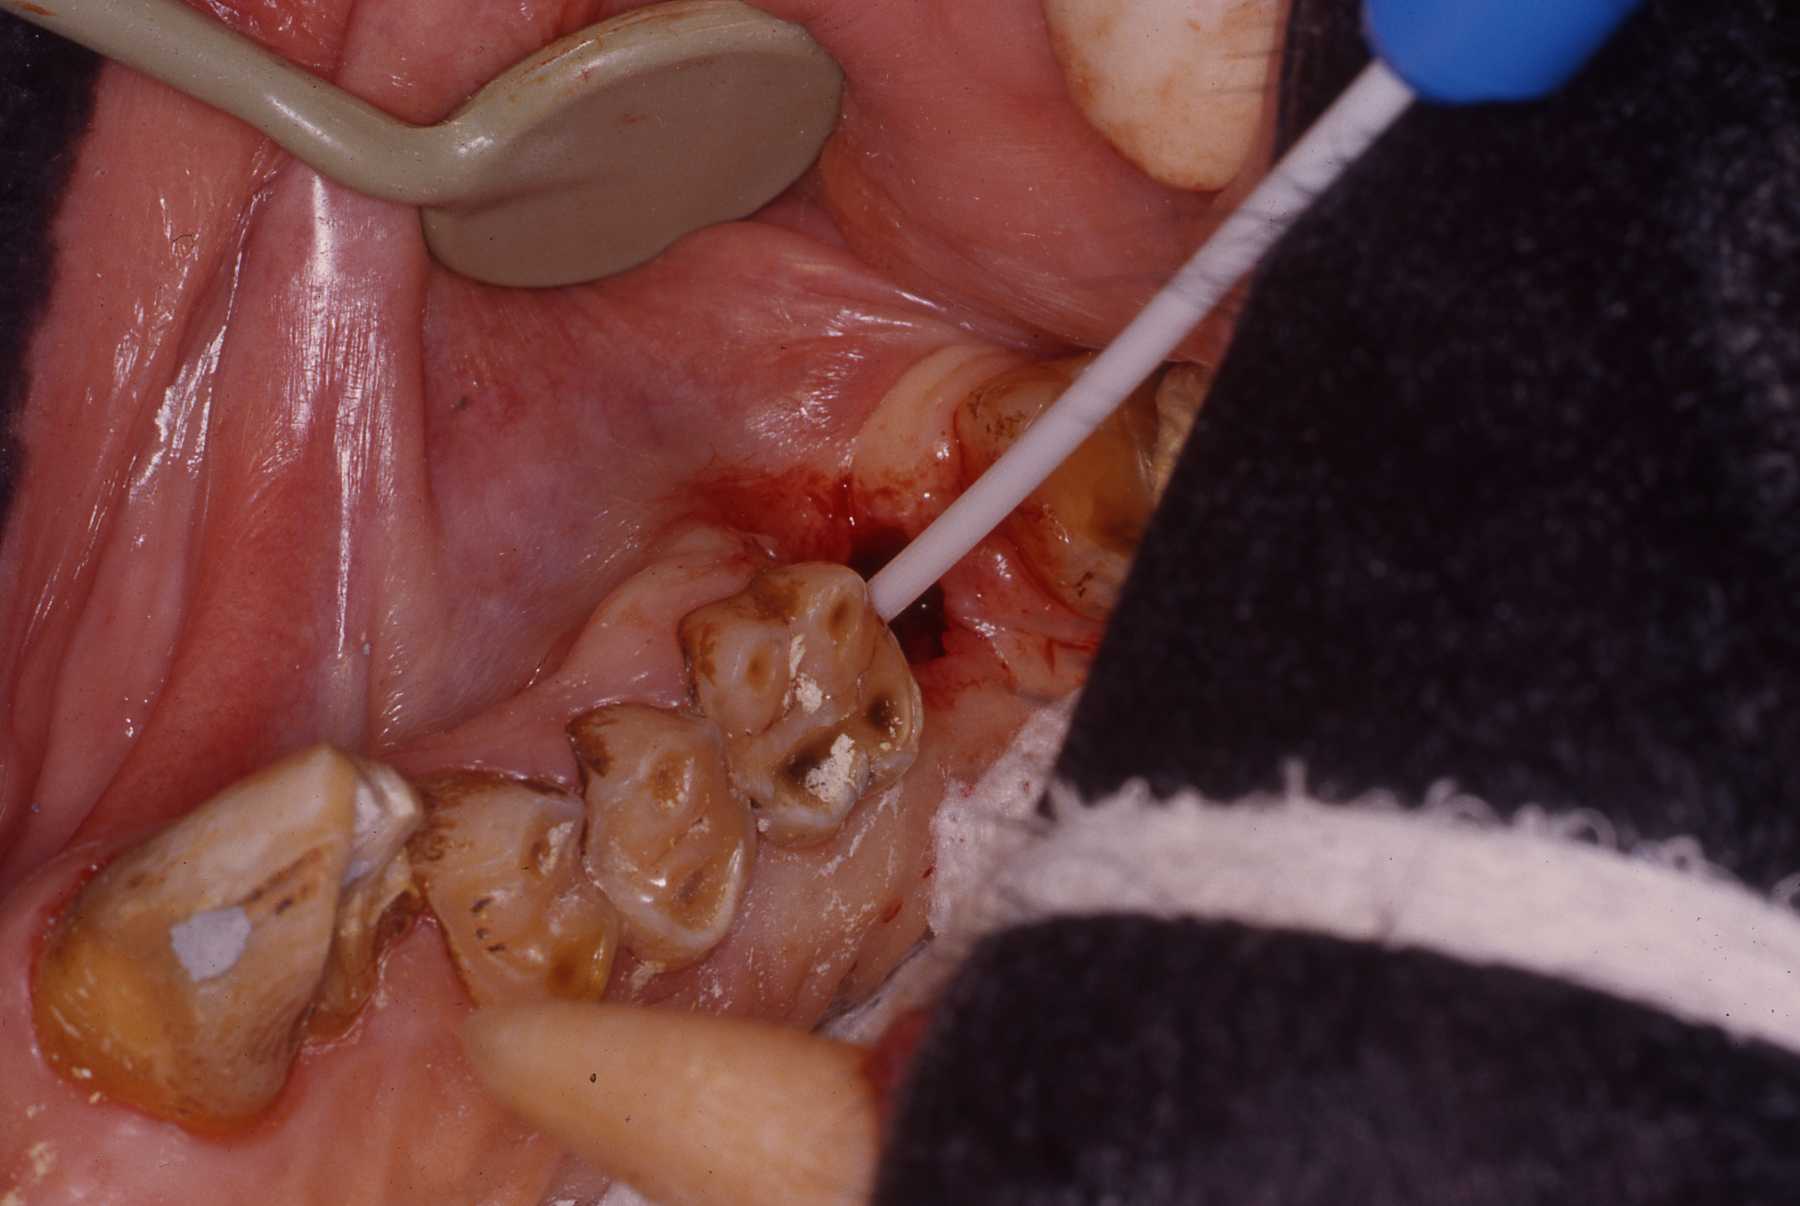

Gorilla Nadami: 13 year old female maxillary canine endodontic procedure

During physical examination fractured maxillary right canine was noted. Chronic fistulos tract noted at junction of attached gingiva and buccal mucosa. Considering age of animal and fact that infected canine pulp had abscessed to the point of forming the drainage tract. I was concerned that the pulp canal would be quite large and that the root apex might be open, not constricted. An open apex would present a challenge to establish a solid stop for a good endodontic fill. Fortunately we did find a solid stop at the apex, permitting a solid fill.

Fistulous chronic drainage tract, found during physical examination, at junction of attached gingiva and buccal mucosa

Fractured maxillary left canine exposed pulp canal